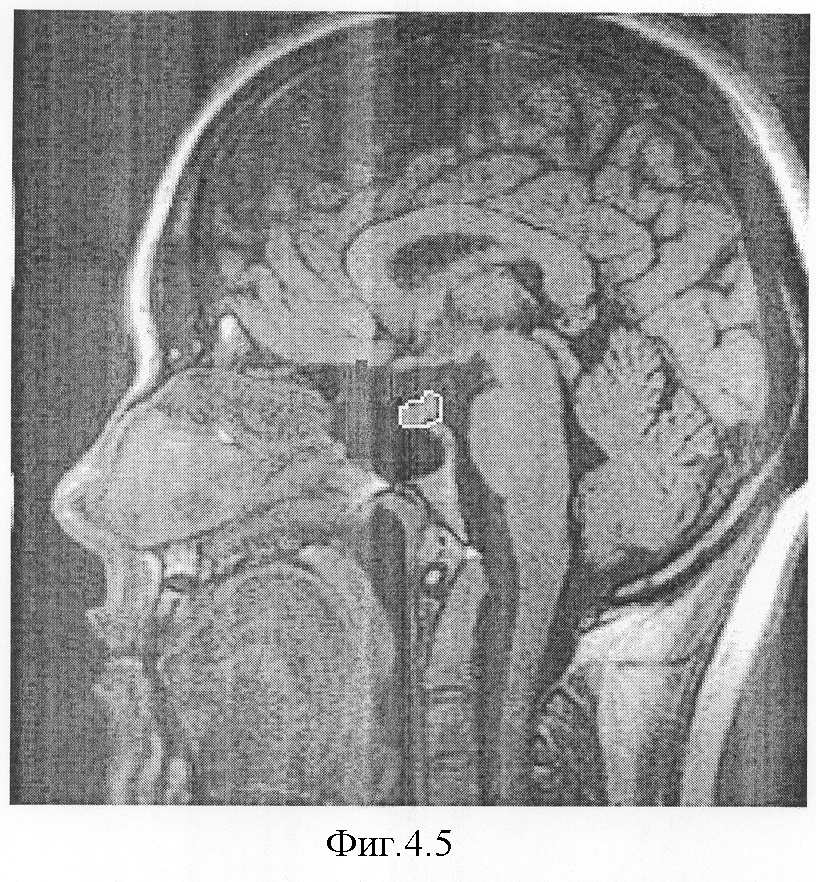

На фиг.4.1-7 показаны результирующие семь изображений, проходящие в сагиттальной плоскости через гипофиз. При этом фиг.4.1 проходит в непосредственной близости от турецкого седла справа, через сифон внутренней сонной артерии, гипофиз не затрагивает;

фиг.4.5 – сагиттальный срез на уровне воронки гипофиза. Площадь обведенного сечения равна 0,51 см2;